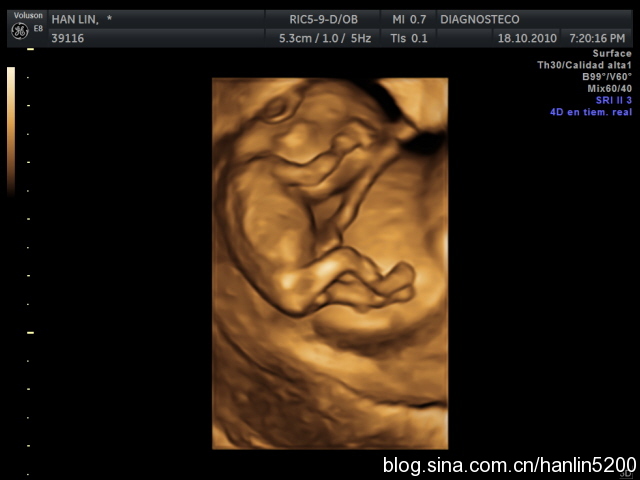

最后来个可爱的四维照!

有没有觉得宝宝可爱到爆!